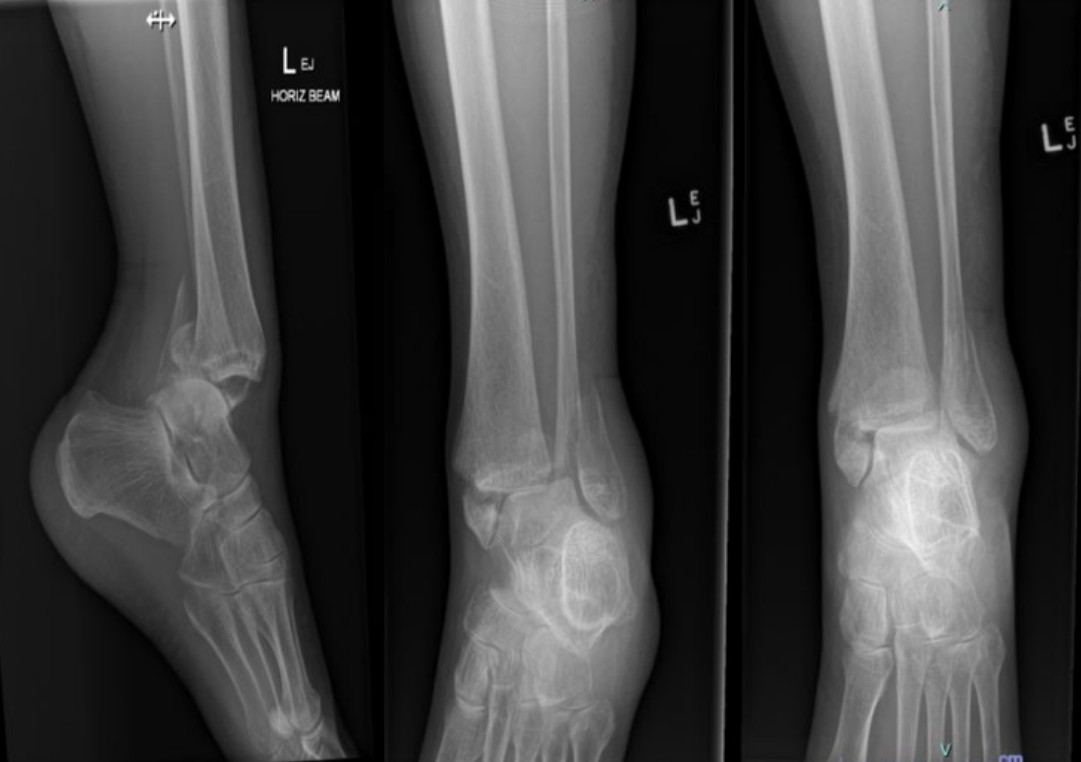

Hot swollen ankle

A 55-year-old man presents with acute atraumatic ankle pain and a low-grade fever.

2024 Term 1 Wk 4 Archived

Trimalleolar ankle fracture-dislocation

A 65-year-old woman presents after slipping on a wet floor and is unable to weight-bear on her left ankle. X-rays …

2024 Term 1 Wk 2 Archived